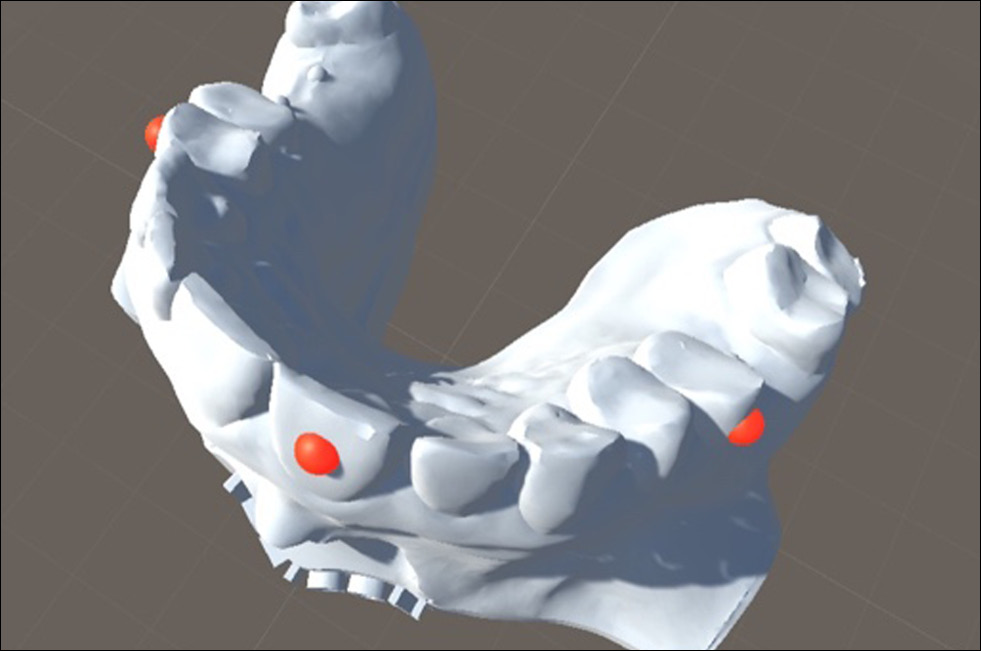

Для определения данной погрешности было напечатано восемь специальных композитных 3D-моделей челюстей, на которые были нанесены по три рентгеноконтрастных метки, соответствующие центральному резцу, левому и правому премолярам (рис. 6).

Рис. 6. 3D-модель челюсти с тремя рентгеноконтрастными метками 1, 2 и 3.

Была выполнена КЛКТ моделей с последующей сегментацией рентгеноконтрастных меток и загрузкой сегментированных изображений в AR-очки в программе Medgital Vision Editor (рис. 7).

Рис. 7. Рентгеноконтрастные метки на этапе сегментации в программе Medgital Vision Editor.